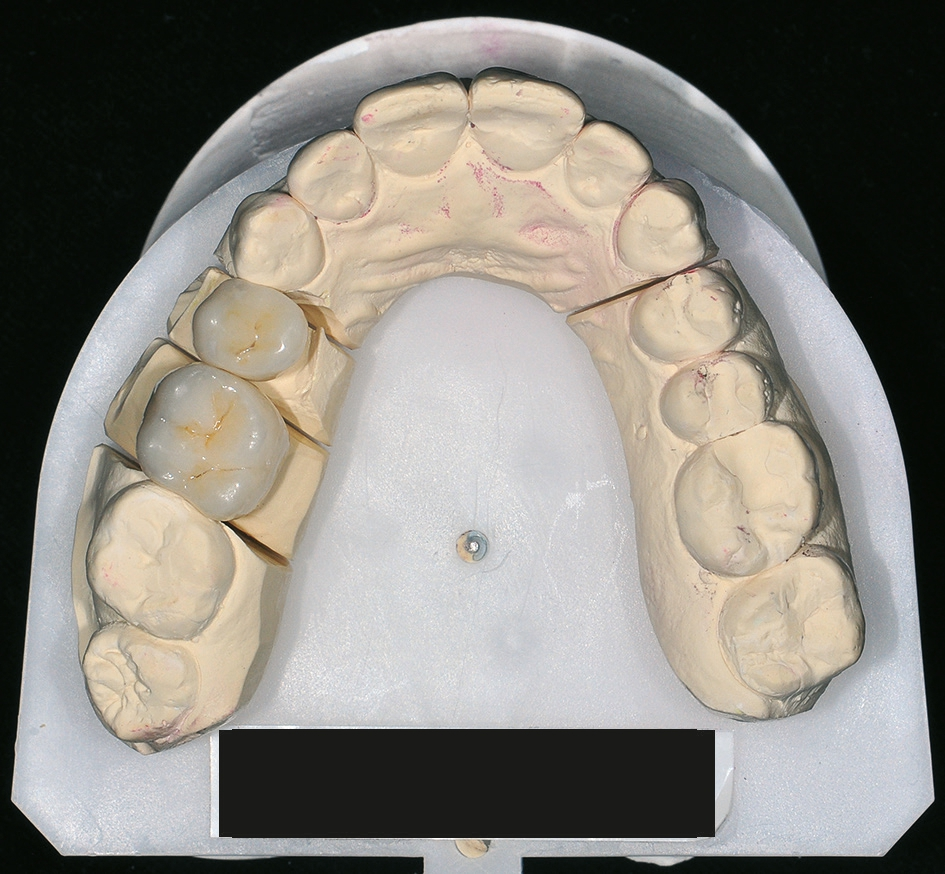

Nach einer komplikationsfreien Einheilzeit von vier Monaten konnte mit der Herstellung des definitiven Zahnersatzes begonnen werden. Hier entschied man sich konsequent für monolithische Kronen aus Lithiumdisilikat, um das Chippingrisiko so gering wie möglich zu halten [12]. Im Zuge der Implantatversorgung wurde nun auch – wie geplant – die metallkeramische Krone an 16 geschlitzt, entfernt und der Stumpf nachpräpariert. Implantatkopf und Zahnstumpf wurden daraufhin zusammen mit A-Silikon analog abgeformt. Für die geschlossene Abformung wurde die Abformkappe (impression.transfer) auf dem Implantatkopf positioniert. Ein deutliches Einrasten signalisierte den lagestabilen Sitz. Für die Modellherstellung rastete das Implantatanalog (lab. replica) ebenso in die integrierte Abformkappe ein. Nach der Herstellung des Meistermodells konnten die beiden Kronen im digitalen Workflow CAD/ CAM-gestützt gefertigt werden. Nach Ausarbeitung, Bemalung und Glasur waren die beiden Kronen für die definitive Zementierung bereit. Die klinische Einprobe der Restaurationen verlief erfolgreich, sodass die Kronen nacheinander mit selbstadhäsivem Befestigungskomposit eingegliedert werden konnten.